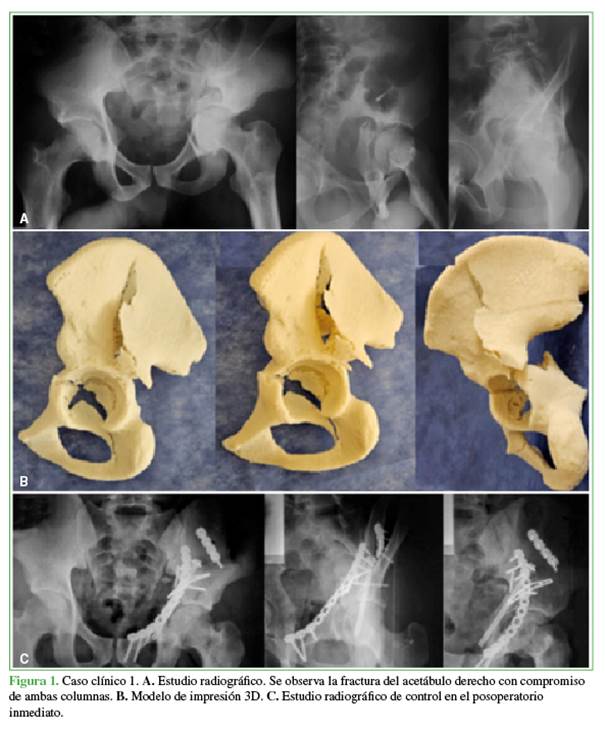

Varón de 20 años de edad que ingresó en el Servicio de Urgencia tras sufrir un accidente en la vía pública (motocicleta-automóvil). Tenía una fractura del acetábulo izquierdo, ambas columnas, con un trazo simple a expensas de la columna posterior y un trazo ilíaco en la columna anterior (clasificación AO 6.2-C1.2) (Figura 1A).

Se procedió a la reducción y osteosíntesis con dos placas de reconstrucción de 3,5 mm, un tornillo canulado de 6,5 mm y una placa tercio de tubo. Se diseñó el modelo con impresión 3D para la planificación quirúrgica, y se realizó la cirugía a los cuatro días de la fractura (Figura 1B y C).

La réplica del acetábulo fracturado nos proporcionó una impresión precisa del volumen, el tamaño y la orientación de los fragmentos óseos de las columnas comprometidas, sirvió para medir la longitud de las placas por colocar y sus respectivos tornillos. El equipo quirúrgico refirió haber optimizado el tiempo quirúrgico y que no se habían producido complicaciones en la colocación de los implantes.